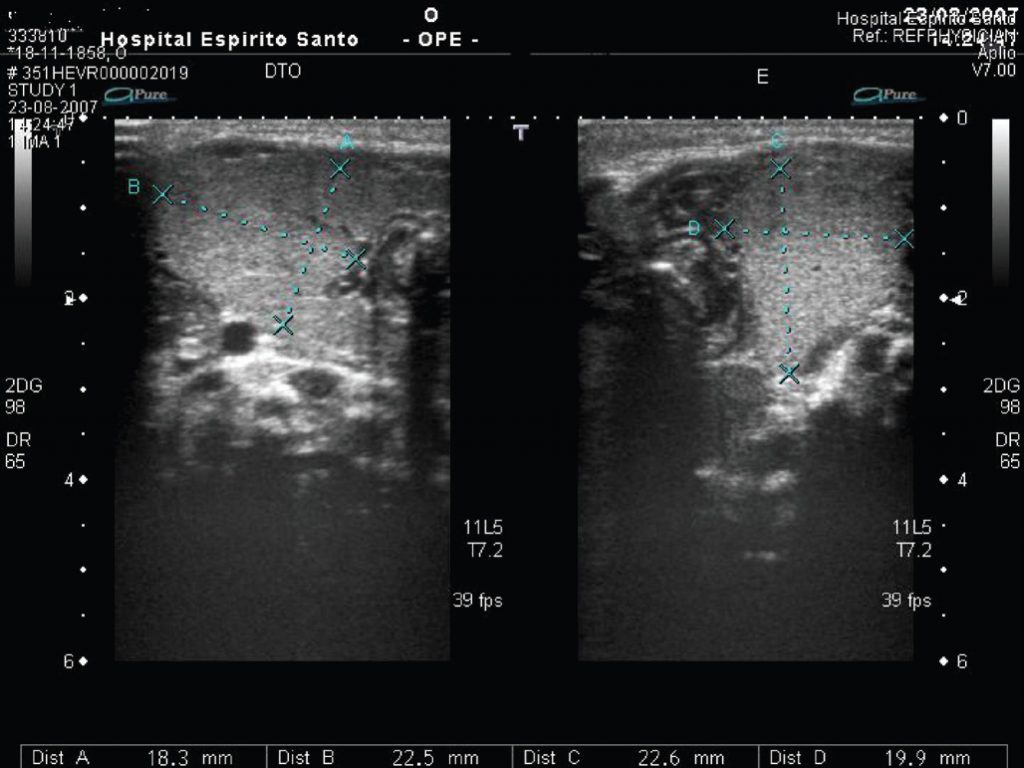

Recém-nascido com massa cervical

O bócio congênito é uma causa rara de massa cervical no recém-nascido podendo resultar de um defeito na síntese de tiroxina pelo feto, ou administração de antitiroidianos ou substâncias contendo iodo durante a gravidez. Na maioria das vezes, acompanha-se de disfunção tireoidiana. É descrito o caso de um recém-nascido a termo, de sexo masculino, com bócio congênito e hipotireoidismo primário. Foi iniciada terapia hormonal de reposição com normalização dos níveis de tiroxina e triiodotironina. Como a investigação materna foi negativa, disormonogênese foi considerada a causa mais provável do hipotiroidismo.